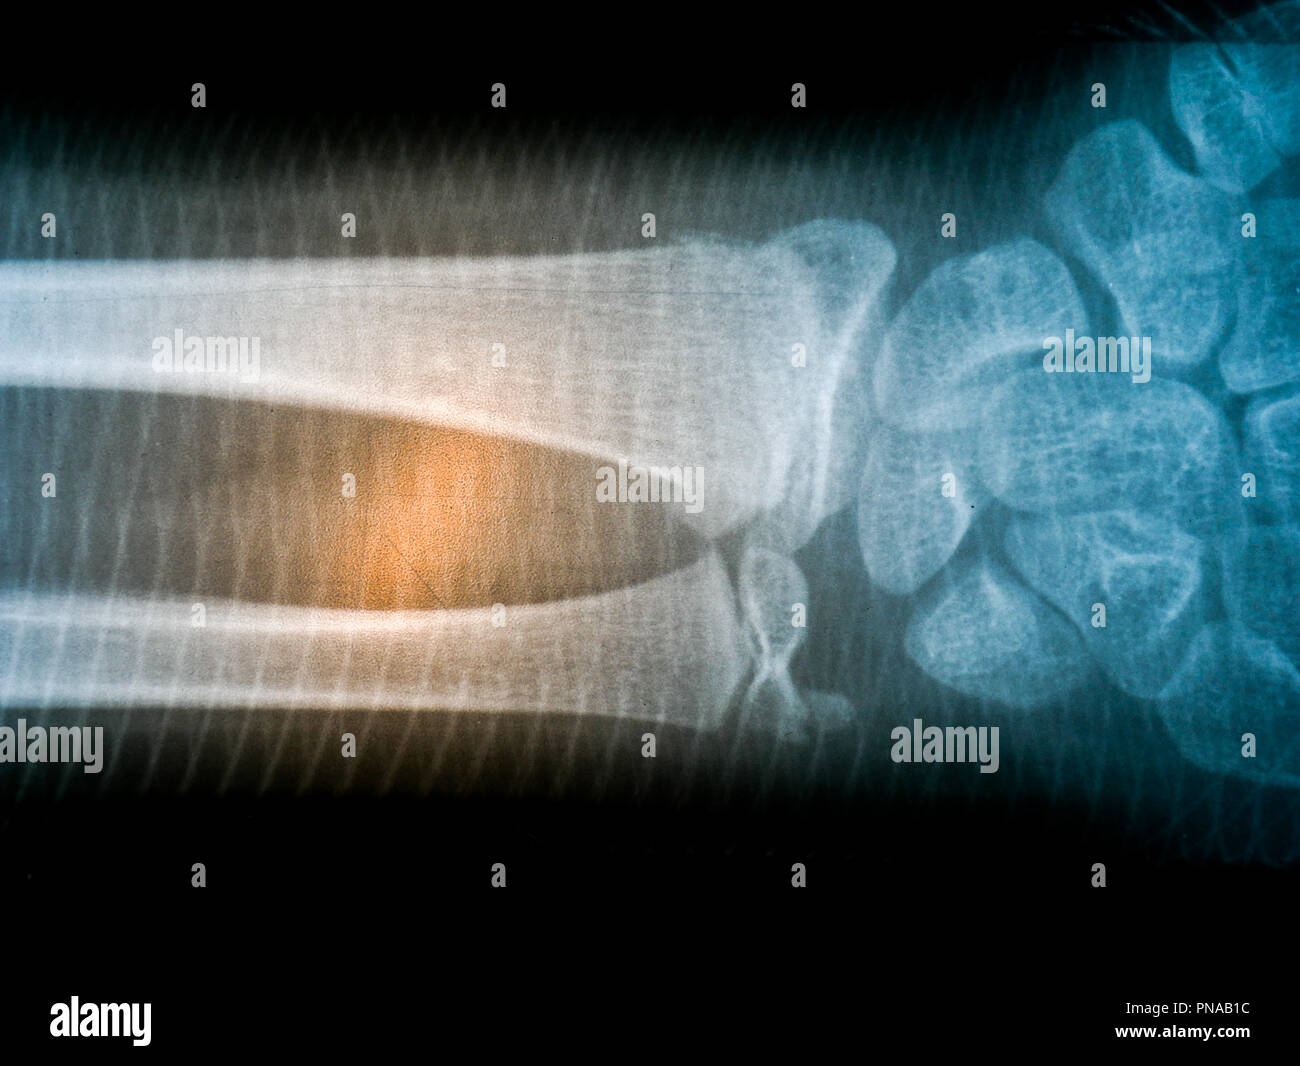

Film Xray Radiograph Show Human Anatomy Stock Photo Edit

Film Xray Radiograph Show Human Anatomy Stock Photo Edit

X Ray Film Skeleton Human Arm Health Medical Anatomy Body

X Ray Film Skeleton Human Arm Health Medical Anatomy Body

X Ray Film Skeleton Human Arm Health Medical Anatomy Body

X Ray Film Skeleton Human Arm Health Medical Anatomy Body

X Ray Film Skeleton Human Arm Health Medical Anatomy Body

X Ray Film Skeleton Human Arm Health Medical Anatomy Body